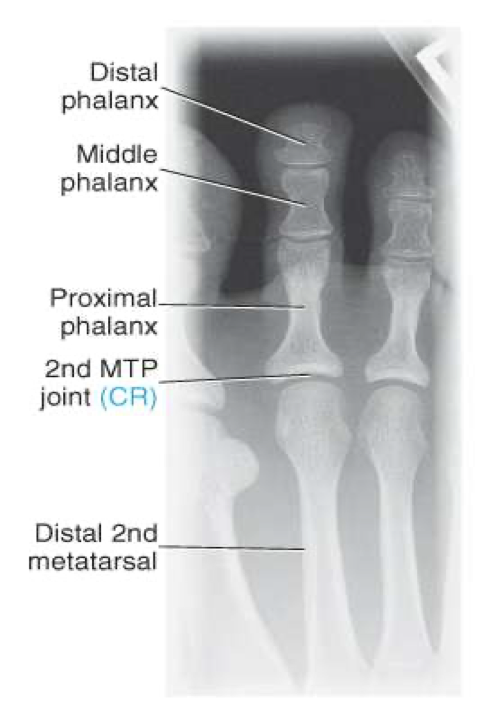

Dorsoplantar (AP) Axial Toes

CR

10-15◦ toward calcaneus

Centered to MTP of interest

Evaluation Criteria of AP toes

Digits and minimum of distal ½ of metatarsal demonstrated

No overlap of soft tissues

IP and MTP joints appear open

No rotation of foot

Equal concavity of phalanges

Optimal exposure factors